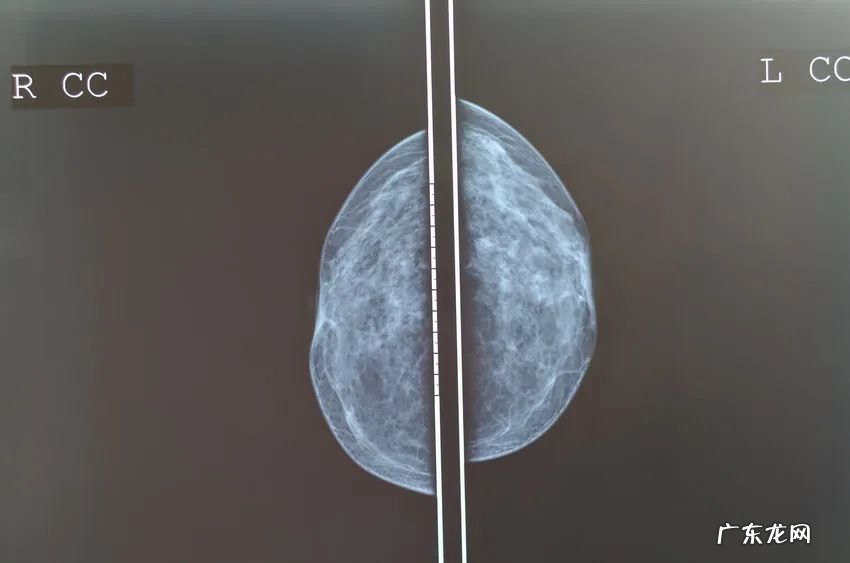

1、乳腺钼靶X线检查

乳腺钼靶X线检查,是乳腺癌筛查中的最重要手段,也是目前诊断乳腺疾病的首选和最简便无创性检测手段,分辨率高,重复性好,留取的图像可供前后对比,不受年龄、体形的限制 。其不仅可以诊断良恶性,还能帮助医生发现早期临床查体未能发现的肿块 。

乳腺癌钼靶X线片可分为直接征象和间接征象两大类:直接征象包括:局限性肿块、成簇微小钙化、局限致密浸润、乳腺结构扭曲、两侧乳腺不对称等 。间接征象包括:皮肤增厚或回缩、乳头及乳晕异常、瘤周水肿、异常增粗的血管等 。